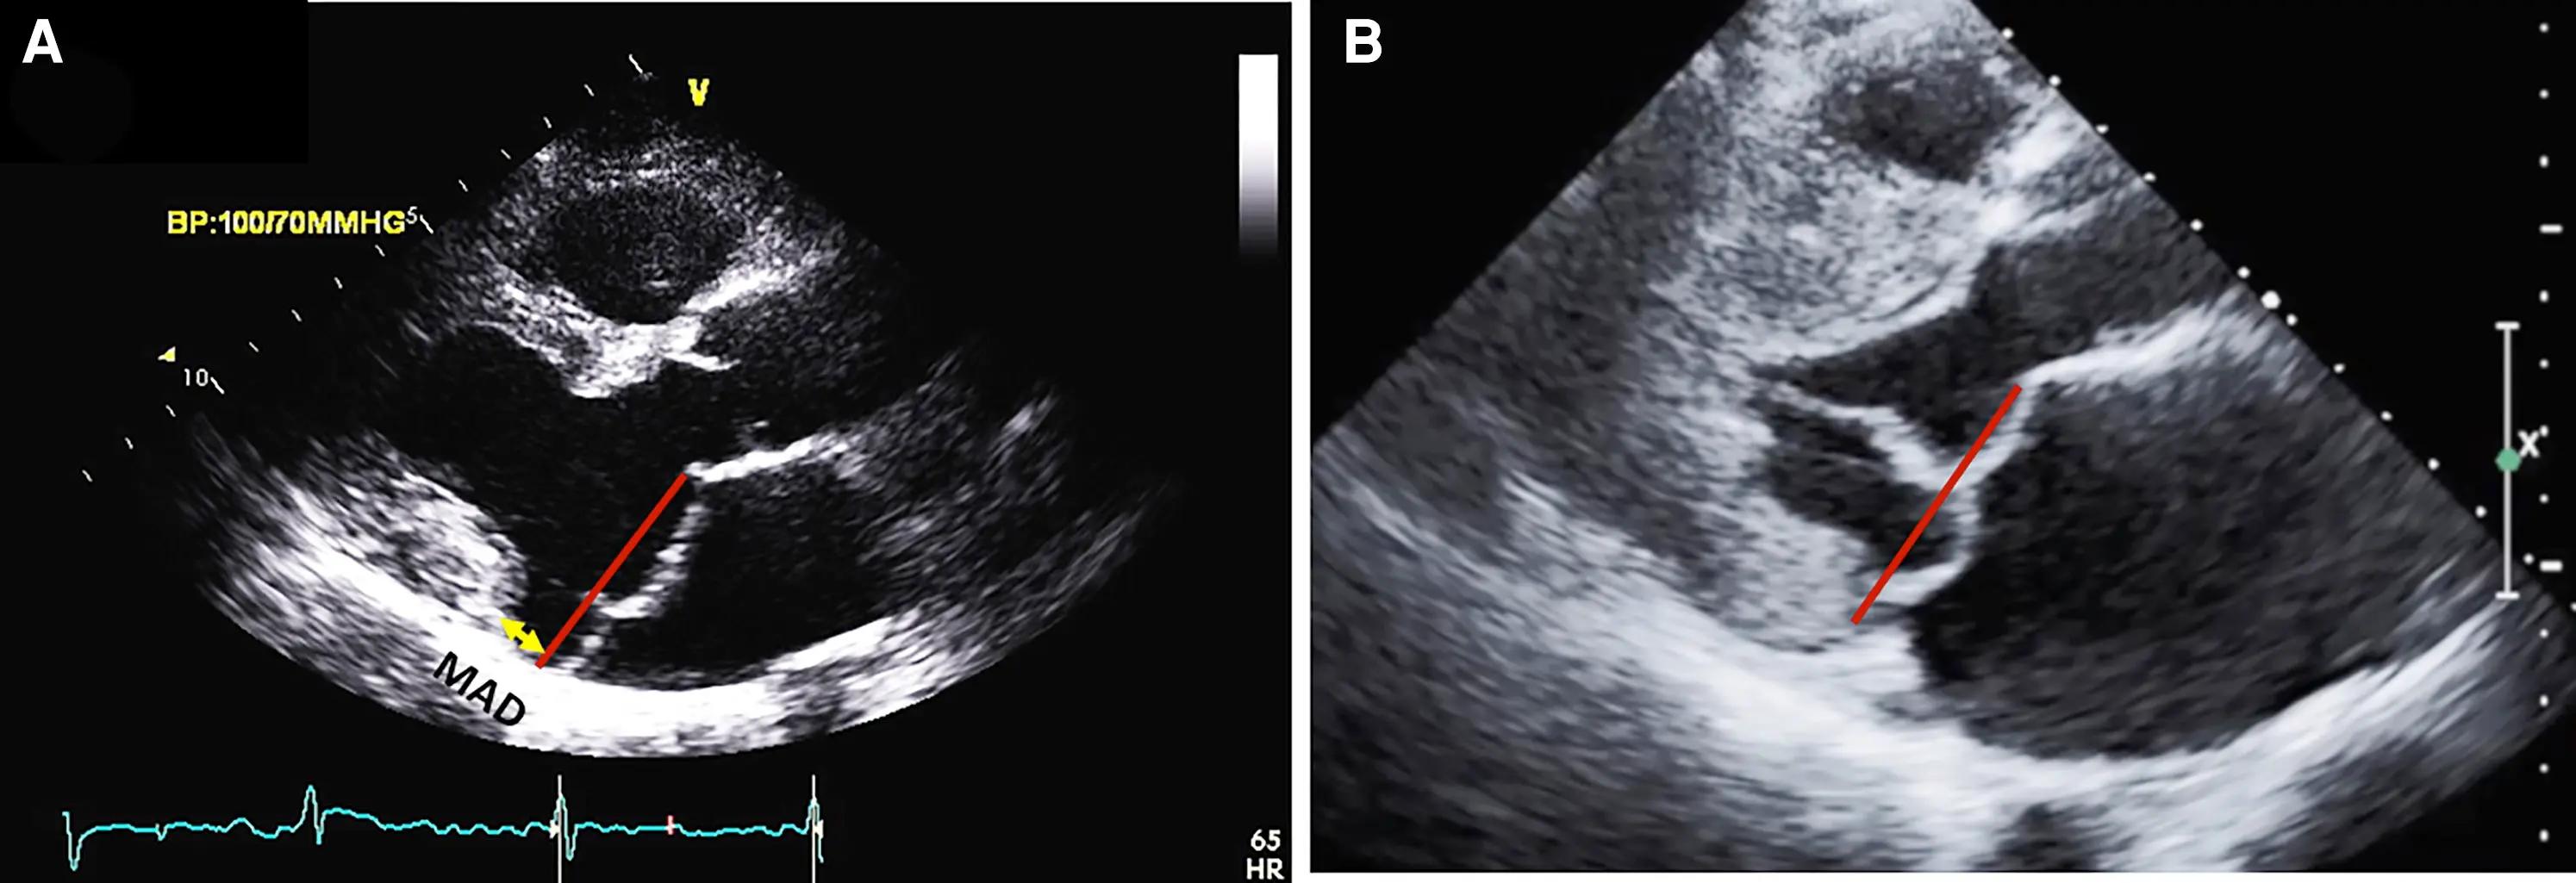

• Mitral Annular Disjunction (MAD)

Mitral Annular Disjunction (MAD)